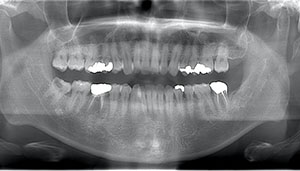

右下の親知らずが疼く症例

- 抜歯前写真(レントゲン)

- 抜去歯の写真(CT画像)

| 抜歯内容 | 右下の親知らずは横向きに生えて埋まっているため、麻酔をし親知らずの奥に切開を入れて歯ぐきを開き、歯を囲んでいる骨を削り歯の頭部分を割って出してから、残った根の部分を取り出して抜歯は終了しました。 歯ぐきを切った部分は糸で縫っています。このケースでは根の先端が神経に近く麻痺のリスクがありましたが事前にCTを撮影し、神経との位置関係を確認していたため、麻痺が残ることはありませんでした。 約1週間後に糸取りを行い、その際も多少の痛みや腫れはありましたが後日その痛みも無くなりました。 |